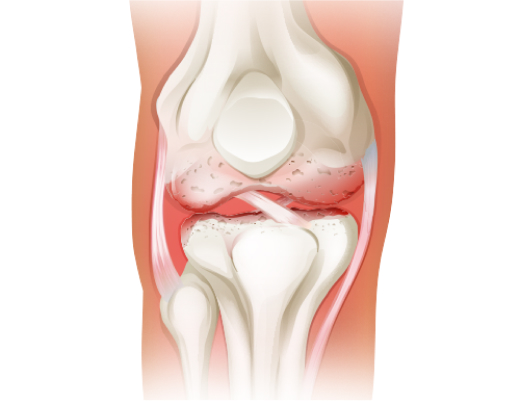

관절 내 연골이 시간이 지남에 따라 닳고 손상되어 뼈와 뼈가 맞닿게 되어 발생하는 염증성 질환을 말합니다.

특히 고령의 환자에게서 많이 발견되며 운동 직업등으로 악화되기도 합니다.

일반적으로 X-ray 검사를 통해 간격 확인이 가능하지만 MRI 검사로 손상 부위나 정도를 정확하게 확인해 치료를 결정할 수 있습니다.